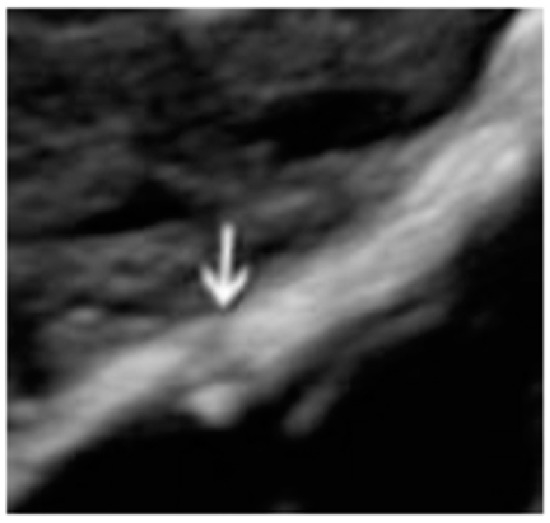

- The presence of hypoechogenic associated tissue (hypoechoic areas surrounding a small cyst area; we called this a “hat”). This tissue does not protrude or invaginate the peritoneal surface.